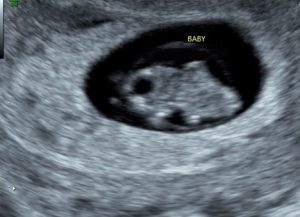

Our first trimester had some obstacles. Early on, an ultrasound technician told us that the embryo would miscarry, and that really crushed us. It felt like we were waiting around for the inevitable, but as each week past, our embryo kept growing and developing properly each week, and eventually hit a point where we felt confident it would stick around, and it did.

During the first trimester, I tried to keep mom in the loop as much as possible, with every feeling I was having- sickness, happiness, tiredness. Mom had never gotten this far herself, so I enjoyed seeing her reaction to all of the milestones. My kids were a bit young to fully understand what was happening, so we did not explain much to them during this trimester.